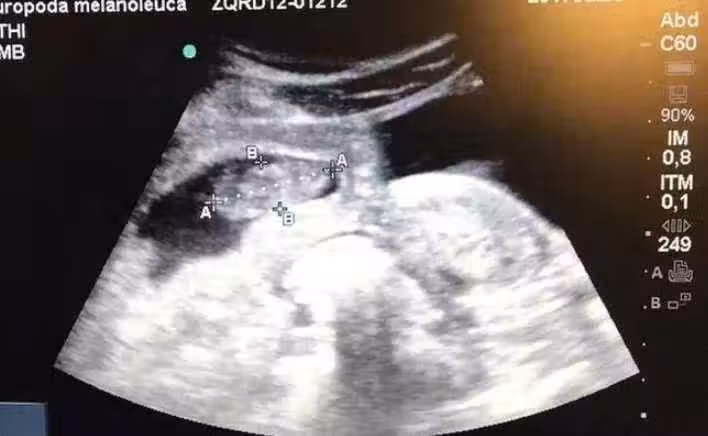

讓我趕緊跟家人商量,我當時很害怕,不知道怎麼辦。

婆家人知道後都讓我把孩子打掉,就連老公都反對我生下來,

但是我不捨得,我決定將孩子生下來,就算是畸形我都認了。

沒有辦法我只有跑到朋友家暫住,好在朋友非常支持我,精心照顧我直到我生產。